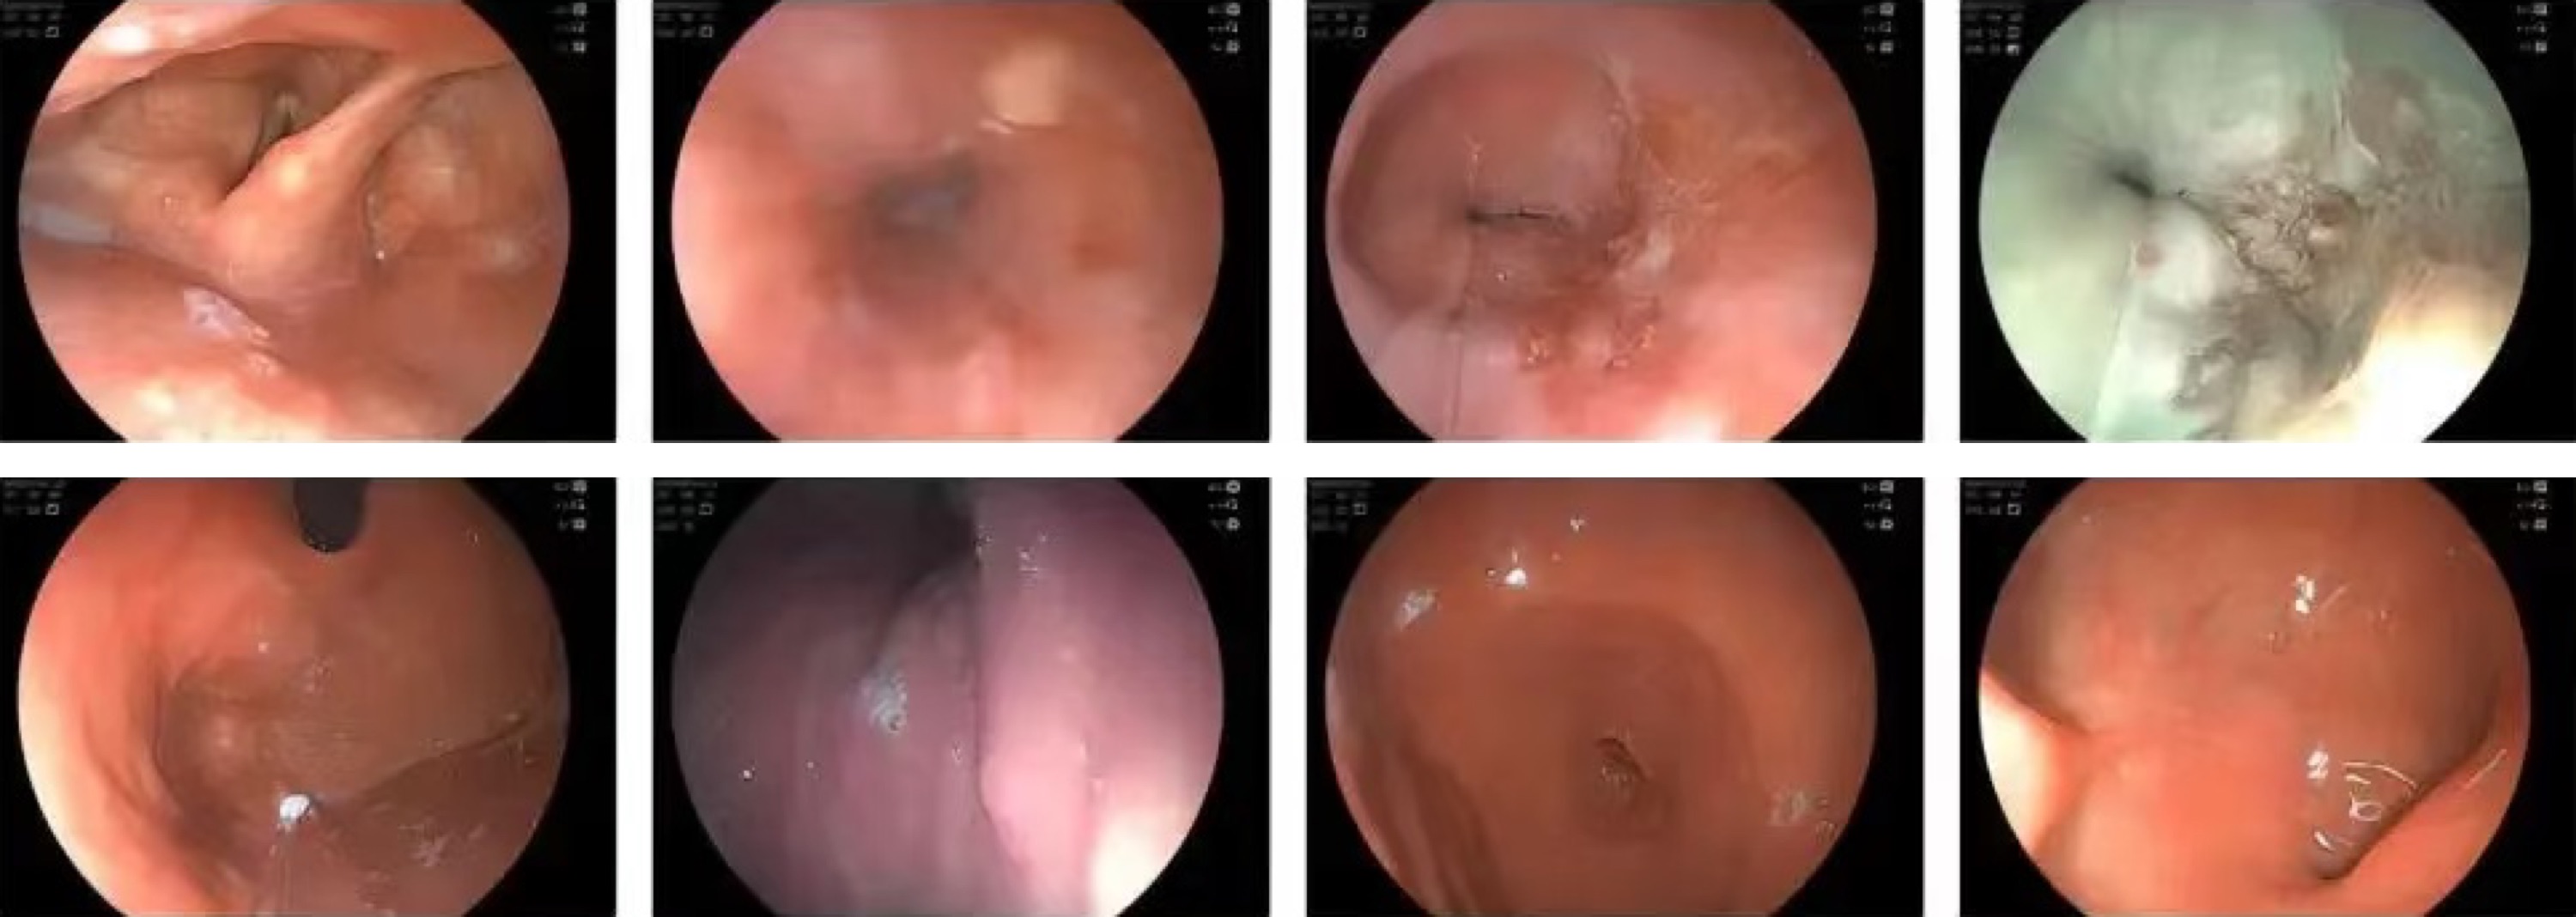

After installation, the hospital immediately arranged patients for clinical trials. The feedback results showed that Lynmou Endoscopy performs excellently in improving examination comfort, reducing examination time, and enhancing diagnostic accuracy. Its Full-Scenario imaging and excellent maneuverability effectively help achieve early screening, diagnosis and treatment.

Hospital director highly praised Lynmou Endoscopy, "Lynmou's products not only demonstrate the innovative strength of domestic medical devices with their excellent performance, but also bring unprecedented efficiency to primary hospitals in the diagnosis and treatment of gastrointestinal diseases. This greatly improves our level of diagnosis and treatment, providing patients with more timely and accurate medical services, while also offering strong technical support to doctors. This is fortunate for both patients and doctors."